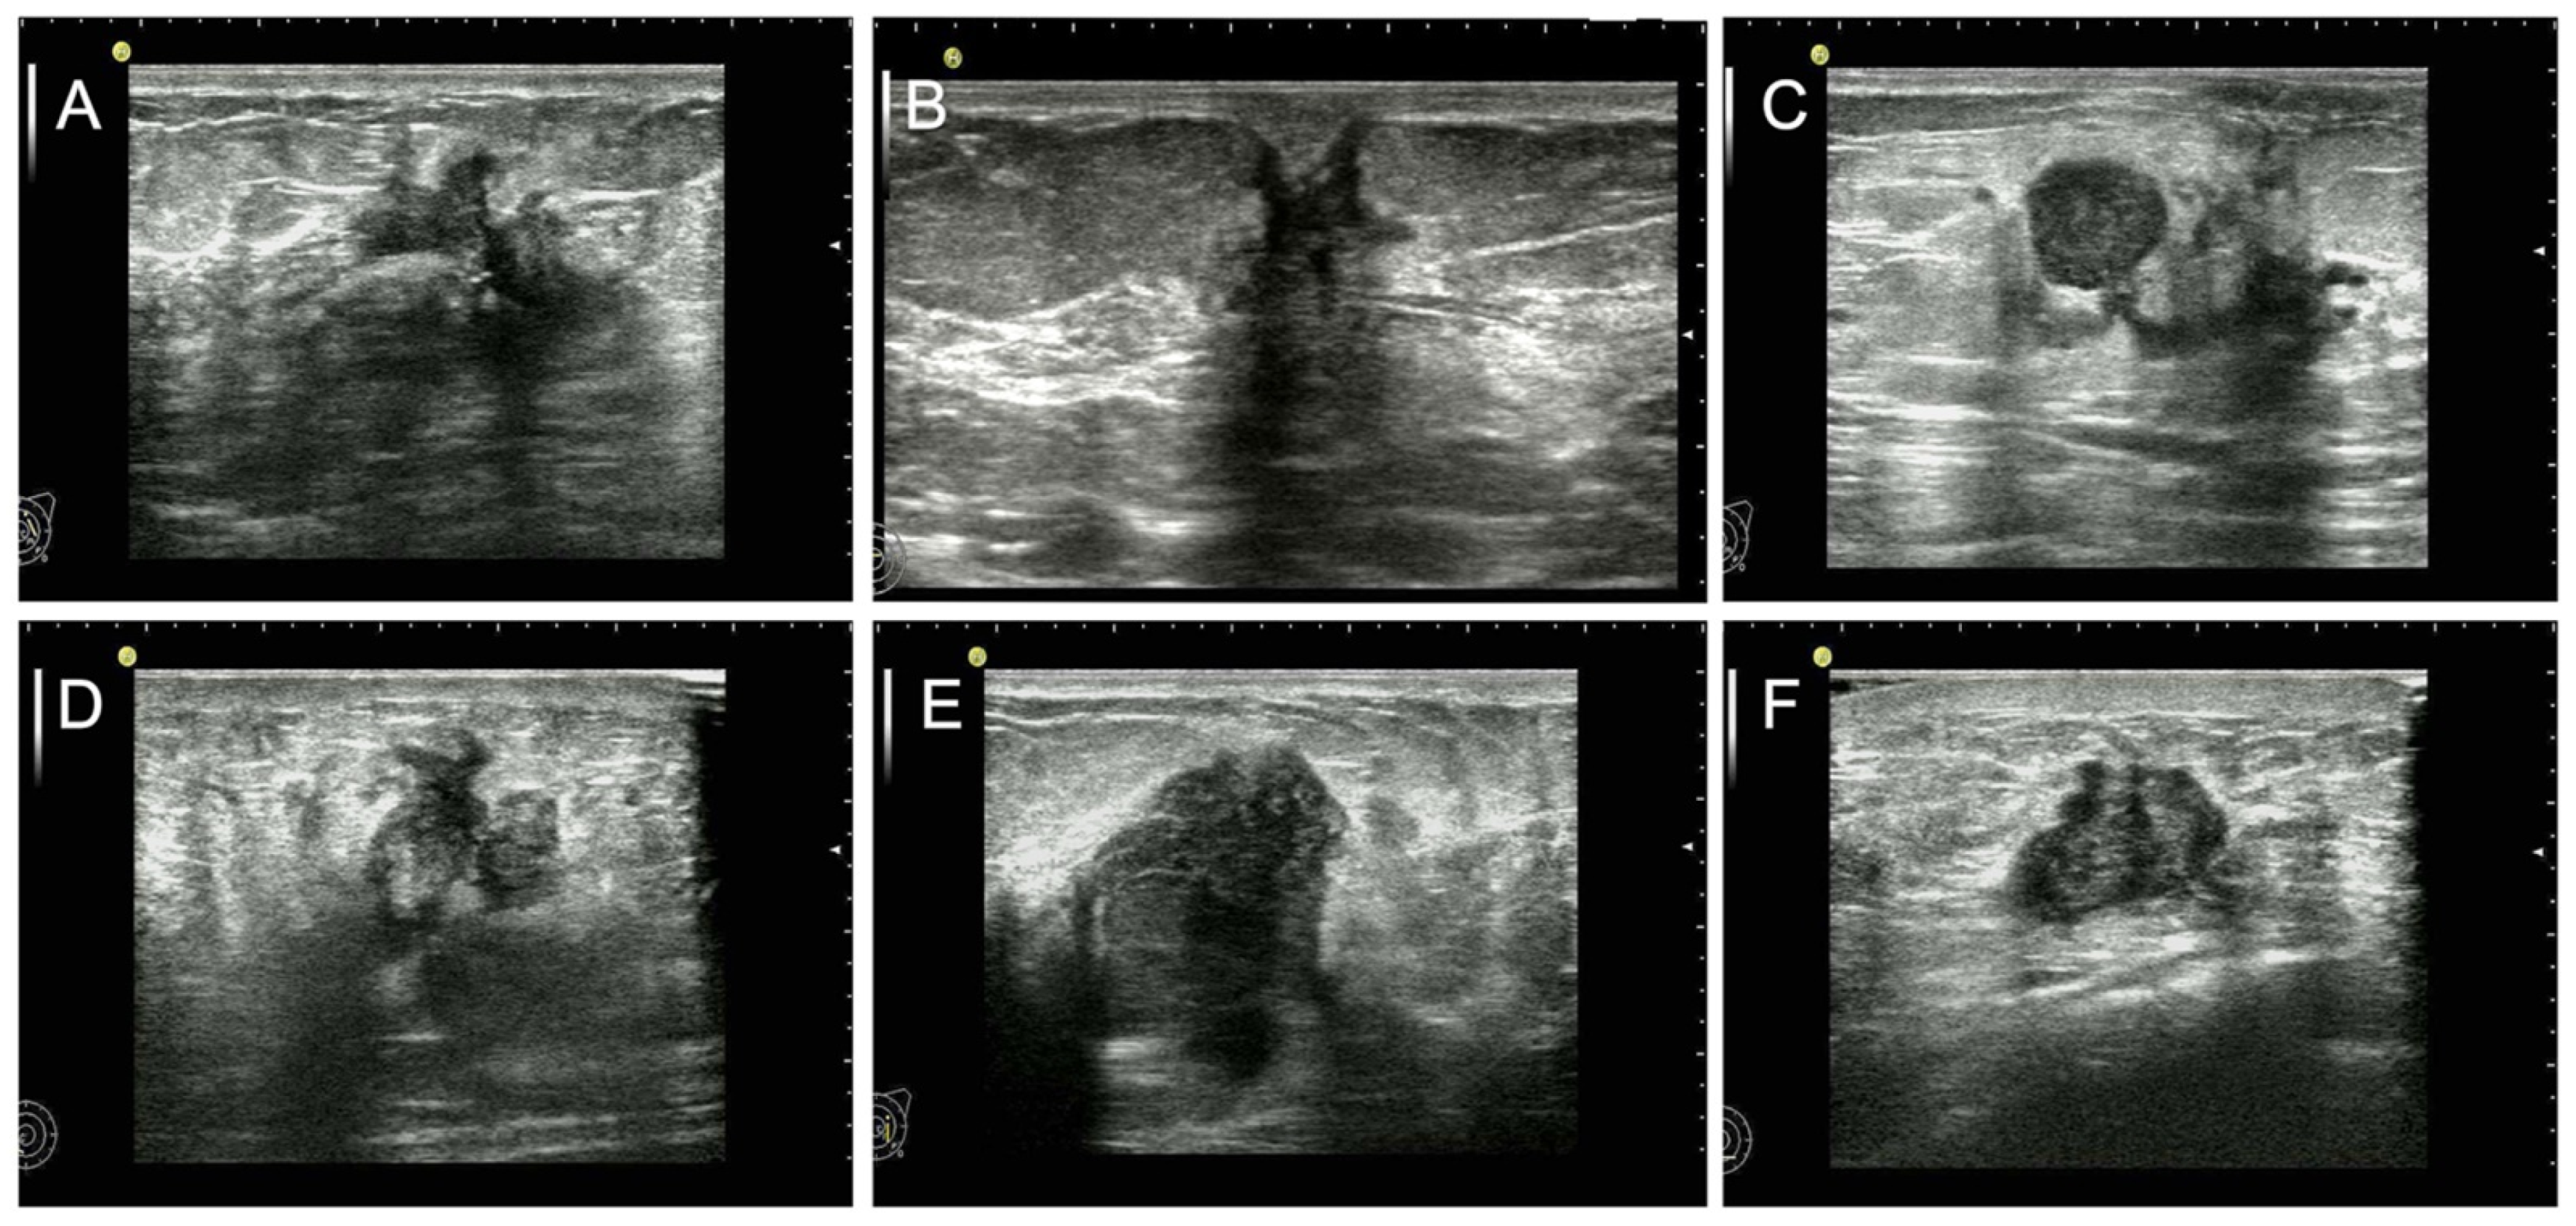

Figure 1.

US feature as independent predictor for short-DFS. We displayed the US images of breast mass from preoperative examination in female patients with invasive ductal carcinoma who suffered from surgical treatment and received postoperatively systemic therapy. (A) The image of the left breast mass from a 48-year-old patient with a short-DFS of 79 months shows the US features of significantly irregular shape and moderately parallel growth orientation. (B) The image of the right breast mass from a 44-year-old patient with a short-DFS of 51 months shows the US features of significantly irregular shape and slightly nonparallel growth orientation. (C) The image of the left breast mass from a 55-year-old patient with a long-DFS of more than 120 months shows the US features of round shape and slightly parallel growth orientation. (D) The image of the right breast mass from a 59-year-old patient with a short-DFS of 58 months shows the US features of significantly nonparallel growth orientation and moderately irregular shape. (E) The image of the right breast mass from a 42-year-old patient with a short-DFS of 35 months shows the US features of significantly nonparallel growth orientation, oval shape, and size of more than 20 mm. (F) The image of the right breast mass from a 58-year-old patient with a long-DFS of more than 120 months shows the US features of oval shape, and parallel growth orientation.